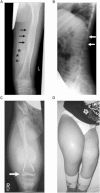

Osteogenesis imperfecta (OI) is a clinically and genetically heterogeneous disorder associated with bone fragility and susceptibility to fractures after minimal trauma. OI type V has an autosomal-dominant pattern of inheritance and is not caused by mutations in the type I collagen genes COL1A1 and COL1A2. The most remarkable and pathognomonic feature, observed in ~65% of affected individuals, is a predisposition to develop hyperplastic callus after fractures or surgical interventions. To identify the molecular cause of OI type V, we performed whole-exome sequencing in a female with OI type V and her unaffected parents and searched for de novo mutations. We found a heterozygous de novo mutation in the 5'-untranslated region of IFITM5 (the gene encoding Interferon induced transmembrane protein 5), 14 bp upstream of the annotated translation initiation codon (c.-14C>T). Subsequently, we identified an identical heterozygous de novo mutation in a second individual with OI type V by Sanger sequencing, thereby confirming that this is the causal mutation for the phenotype. IFITM5 is a protein that is highly enriched in osteoblasts and has a putative function in bone formation and osteoblast maturation. The mutation c.-14C>T introduces an upstream start codon that is in frame with the reference open-reading frame of IFITM5 and is embedded into a stronger Kozak consensus sequence for translation initiation than the annotated start codon. In vitro, eukaryotic cells were able to recognize this start codon, and they used it instead of the reference translation initiation signal. This suggests that five amino acids (Met-Ala-Leu-Glu-Pro) are added to the N terminus and alter IFITM5 function in individuals with the mutation.